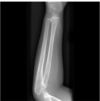

Lucent fracture lines. Most fractures appear as a radiolucent line.

Not a lucent line. Not a fracture. Flare of tibia.

Yes, fracture lucent line.

Important to know. Lucent line goes into joint.

Displacement fx. NOT angulated! If both ends are touching then nondisplaced, if not touching then displaced.

Nondisplaced Fracture. still lines up.

Nondisplaced Fracture. still lines up. can see a lucent line.